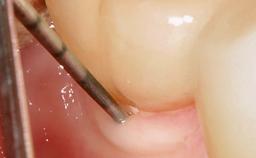

This case describes both a surgical and an anti-infective approach for the management of peri-implantitis, including treatment of the entire dentition to eliminate any deep periodontal pockets that could serve as reservoirs for bacterial re-colonization at the implant site. A 65-year-old female patient was referred to the periodontist in 2013 for assessment and management of an infection at implant 12. On examination, probing depths at implant 12 were 11 mm with suppuration and bleeding on probing.